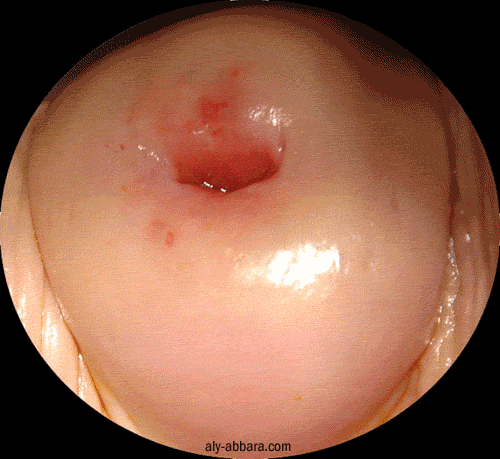

Polype endocervical pédiculé, bénin et accouché par l'orifice externe du col utérin

Aspect avant et après la polypectomie (ablation du polype)

A comparer au polype sessile du l'endocol